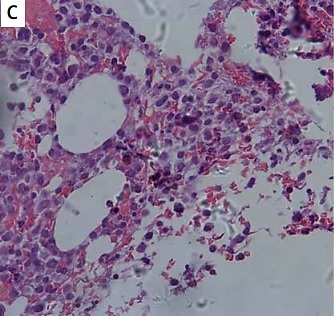

A 74-year-old man with a history of hypertension presented to the rheumatology department with polyarticular swelling and tenderness, followed by progressive pain in the hip. Physical examination revealed stiffness of the joints of both hands in a fixed position with limited joint motion. Ultrasound of the hand joints showed symmetric synovitis with bone erosion involving the proximal interphalangeal joints, metacarpophalangeal joints, and wrist joints. Subsequent magnetic resonance imaging of the hip revealed a swollen mass of soft tissue around the right hip joint, measuring approximately 16 × 16 × 10 cm, along with severe synovial hyperplasia in both hips (Figure 1 A). Histopathological examination showed massive amyloid deposition and calcification (Figure 1 B, Congo red staining), along with massive synovial cell proliferation and inflammatory cell infiltration (Figure 1 C, Crystal violet staining), and immunohistochemistry showed positivity for λ chains (Figure 1 D). Laboratory tests were negative for rheumatoid factor, anti-citrullinated protein antibody, antinuclear antibodies, ANCA, HLA-B27; hemoglobin was 80 g/l, blood calcium 3.11 mmol/l, serum creatinine 322 µmol/l, serum β2-microglobulin 13943.7 ng/ml, urine protein was 5.85 g/day. Inflammatory indicators showed that erythrocyte sedimentation rate of 60 mm/h and C-reactive protein of 43.2 mg/l.

A – Magnetic resonance imaging of the hip revealed a swollen mass of soft tissue around the right hip joint, measuring approximately 16 × 16 × 10 cm, along with severe synovial hyperplasia in both hips. Histopathological examination showed massive amyloid deposition and calcification (B, Congo red staining), along with massive synovial cell proliferation and inflammatory cell infiltration (C, Crystal violet staining), and immunohistochemistry showed positivity for λ chains (D)